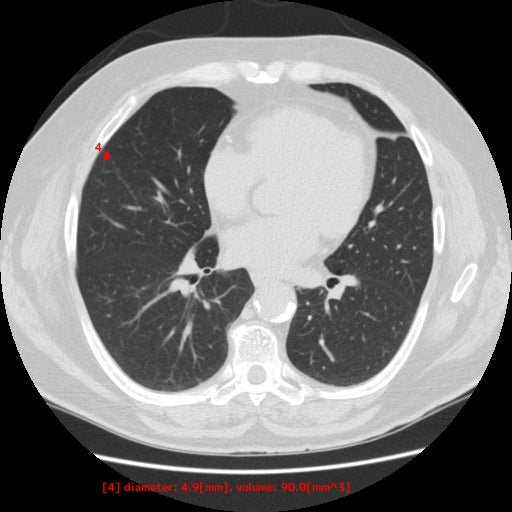

本製品は、胸部CT画像から肺野領域の組織について、使用者が設定した基準値に基づくCT値から「関心領域」を抽出し、その体積と最大径を自動計測します。計測した最大径が閾値以上となった場合には、画像上に色付けして表示します。この抽出・計測・表示機能は、医師が胸部CT画像を対象に読影診断を行う際に併用することで、肺野周辺組織とCT値が異なる肺結節等の視認性向上に寄与することが期待されます

【EIRL Chest CTによる表示例】

① 標準線量CT